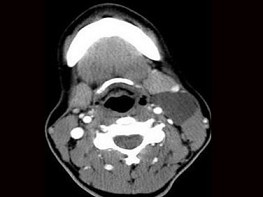

8.患者腫塊圖像及影像學檢查結果見下圖,本患者應考慮為  (    )

正確答案:8.A;9.A